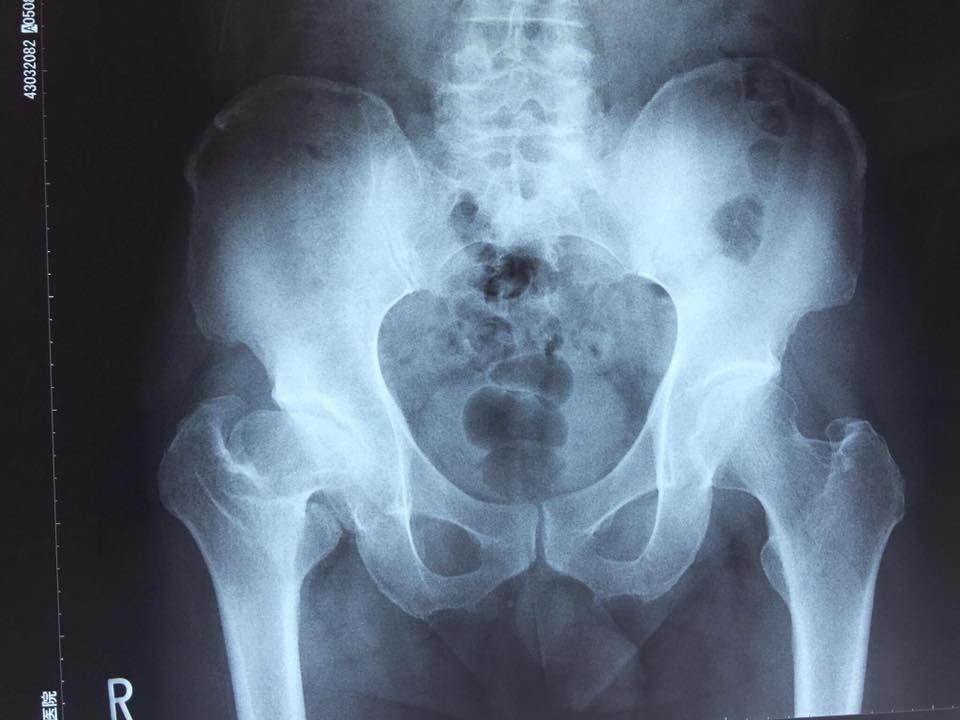

レントゲン写真を見せられ目を覆いたくなるほどの

股関節の症状だと思いきや、実際その方自身

痛みを訴えるのは今回は腰痛だったんだ。

ご覧の通りレントゲン写真では大腿骨頸部は

真横を向いて寛骨臼に侵入している。

元々の脚長差は1センチか1.5センチほどの差

だったけど今は4センチ以上あるそうなんだ。

だからこの大腿頚部の向いている角度が

これを作っているのは言うまでもない。